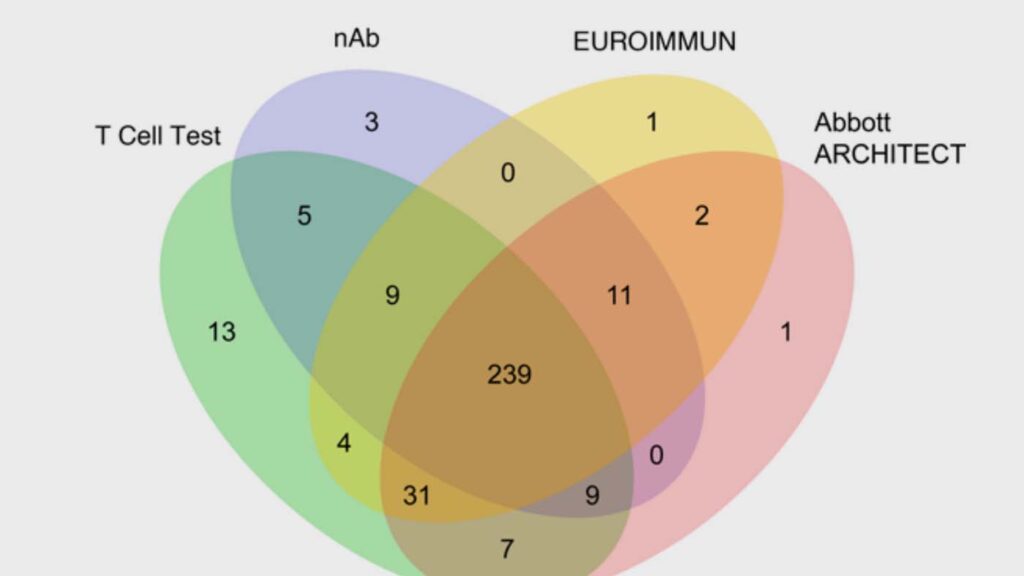

T-cell receptor (TCR) sequencing identifies prior SARS-CoV-2 infection and correlates with neutralizing antibody titers and disease severity

The blood levels of neutralizing antibody titers (nAb) closely correlate with the protection provided by an effective vaccination. But nAb assays are challenging to perform at a large scale. This research instead applied a TCR sequencing assay on a standard blood sample to assess T-cell response to SARS-CoV-2 infection. It found that the magnitude of the SARS-CoV-2-specific T-cell response strongly correlates with nAb titer, as well as with clinical indicators of disease severity including hospitalization, fever, or difficulty breathing, thus demonstrating the utility of a TCR-based assay.